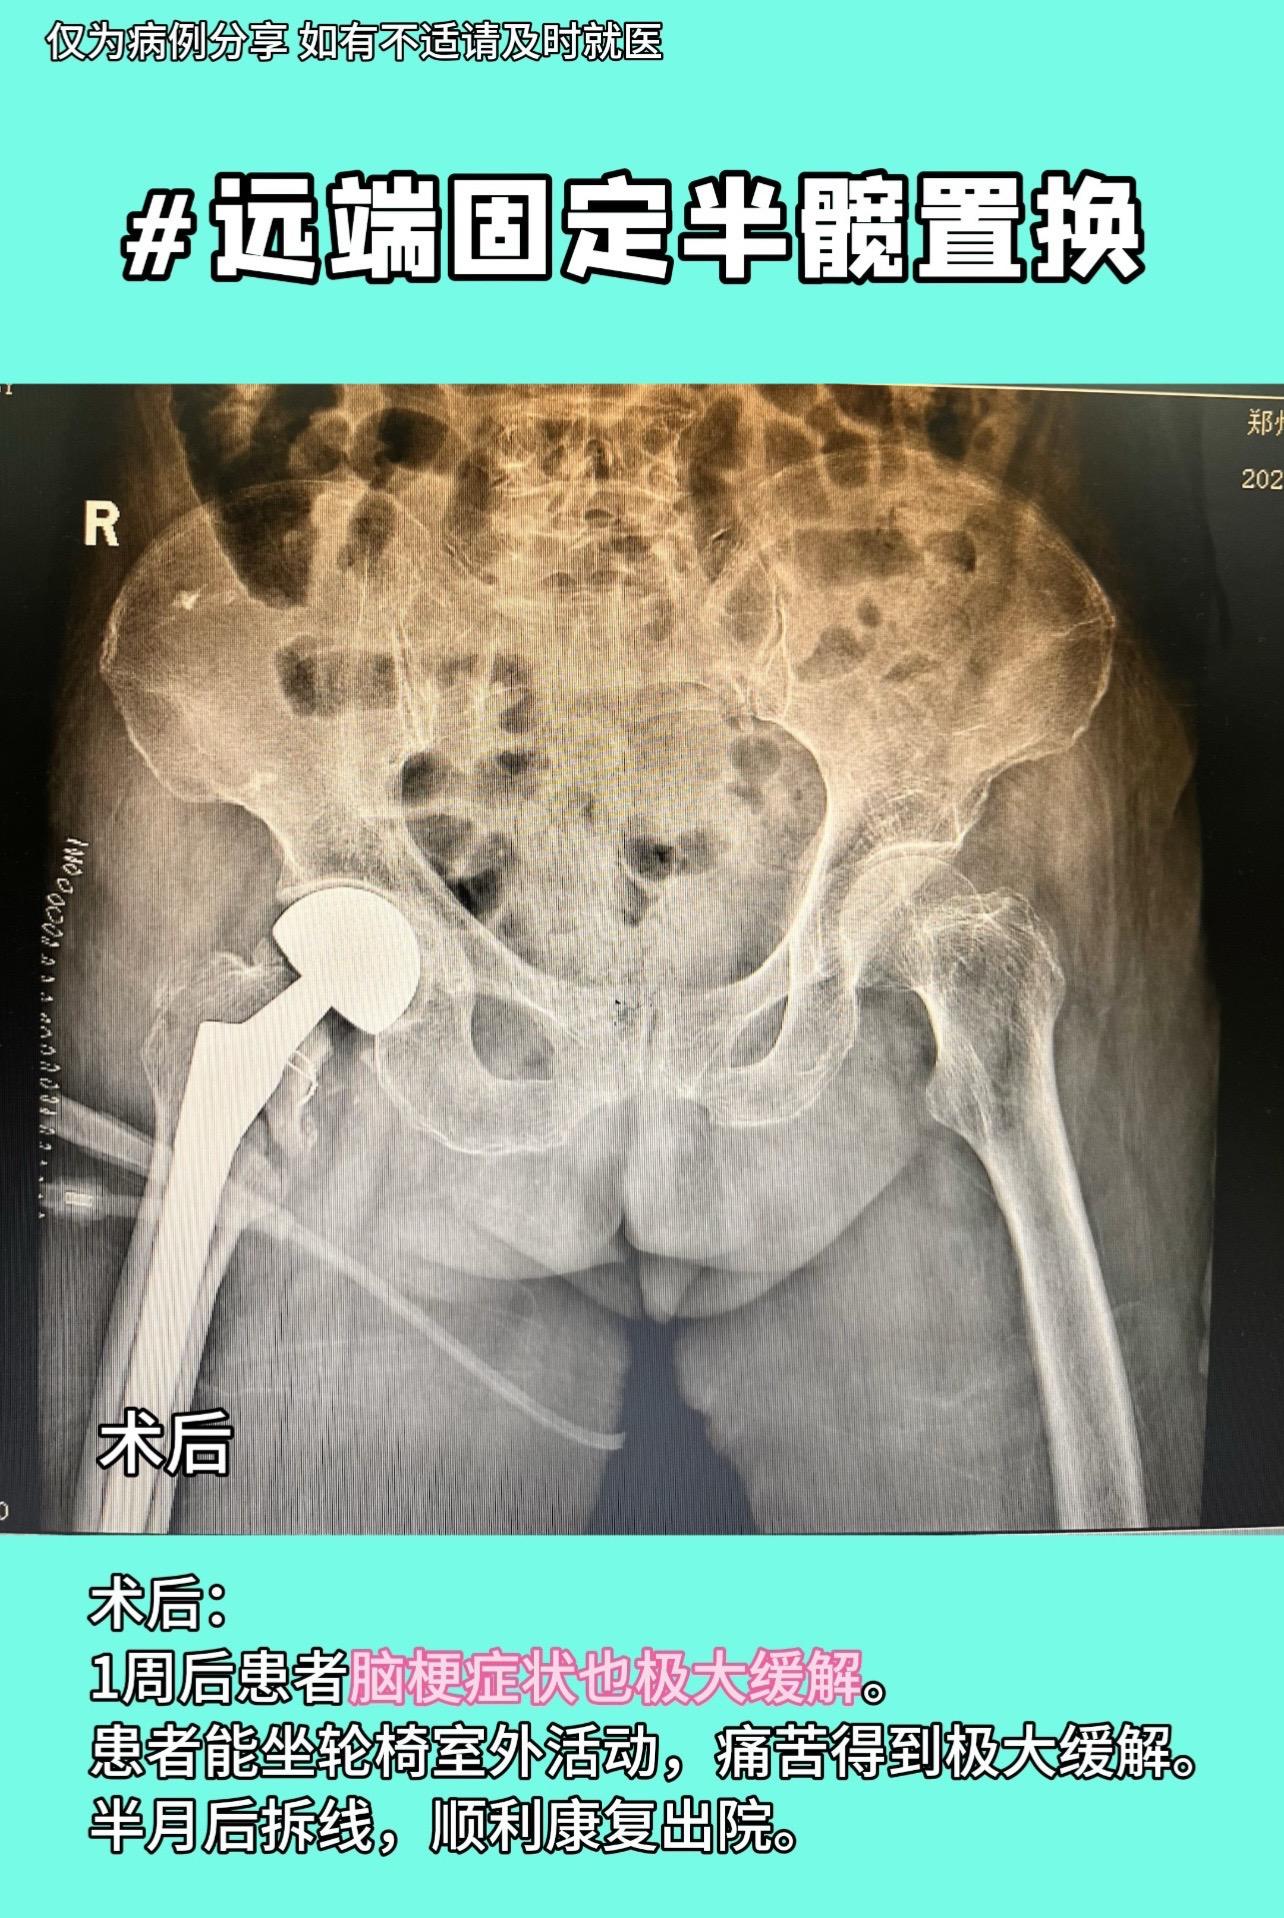

96岁老人,摔倒髋部骨折,手术风险巨大,县医院市医院建议转院。入院后检查:脑部多发急性脑梗,神内会诊示手术风险巨大,但不做手术卧床会再加重脑梗,陷入两难。与家属充分沟通,家属愿担风险一试。麻醉采用局部神经阻滞➕腰麻,仅麻醉准备就2个半小时,手术采用远端固定半髋置换。手术时间约1小时,术后积极治疗脑梗,1周后患者脑梗症状也极大缓解。患者能坐轮椅室外活动,痛苦得到极大缓解。半月后拆线,顺利康复出院。